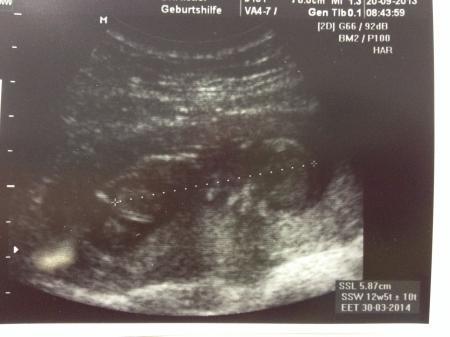

Guten morgen an alle, mein FA-Besuch war super. Es wurde voll lange Ultraschall gemacht. Die Nackenfalte ist total unauffällig und man hat den kleinen Krümel sogar schlucken sehen...auch wenn es geschlafen hat...und zwar mit angezogenen Beinen, damit man auch ja keine Vermutung abgeben kann, außerdem war meine Blase nicht voll genug um wirklich alles detailiert zu sehen Aber vollkommen egal, der Krümel ist gesund und das ist das wichtigste!!! Ach ja, es ist schon 5,87 cm SSL groß(lt. Ultraschall wäre ET der 30.03. aber wir ändern ihn jetzt nicht mehr)...total faszinierend wie schnell das geht. Mein FA meinte jetzt auch, jetzt geniesen Sie die Zeit bis es unangenehm wid Hach, ich bin so glücklich! Langsam wird es echt realistisch das mein Mann und ich im April zu dritt sein werden